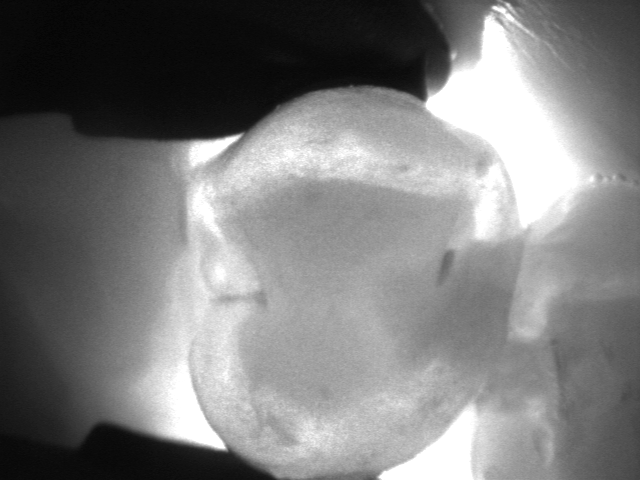

La videocamera digitale sulla testa del manipolo rileva luci ed ombre all’interno del dente e proietta l’immagine ottenuta sullo schermo del pc in tempo reale: le parti sane, che consentono il passaggio della luce, risultano chiare, quelle lesionate, che al contrario lo bloccano, si distinguono nettamente come aree scure.

Le immagini in bianco e nero, altamente dettagliate, ricordano molto le radiografie ma di fatto sono state del tutto ottenute senza radiazioni, soltanto per transilluminazione laser!

Vedere l’estensione della lesione, se ancora soltanto sullo smalto o già sconfinata in dentina, e la sua esatta posizione sono informazioni fondamentali per impostare una terapia che sia il più possibile conservativa.

I fermo immagine ottenuti servono a motivare il paziente e rendere più comprensibile il piano di trattamento. Nel caso di lesioni iniziali permettono, inoltre, un attento monitoraggio nel tempo, ad ogni successivo controllo.

Consente la diagnosi precoce di cracks (incrinature, fratture), demineralizzazioni e carie (occlusale, prossimale o secondaria sotto vecchi restauri), quando sono sopragengivali.

Evidenzia la carie con più sensibilità e attendibilità della sola ispezione visiva e molto prima che appaia alle radiografie, rendendo possibili trattamenti profilattici o minimamente invasivi.